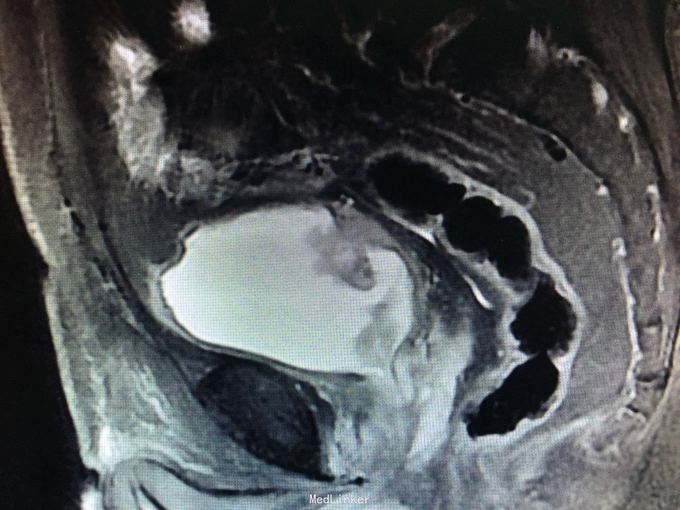

肉眼血尿一周余。 患者一周前无明显诱因出现肉眼血尿。遂于我院就诊,门诊膀胱镜提示:膀胱左侧巨大占位,未窥及基底部。今为进一步治疗收入我科。 九年前于上海行膀胱部分切除术。 81岁,男性患者

查体:无殊。 门诊MRI提示膀胱多发肿瘤,累及深肌层。